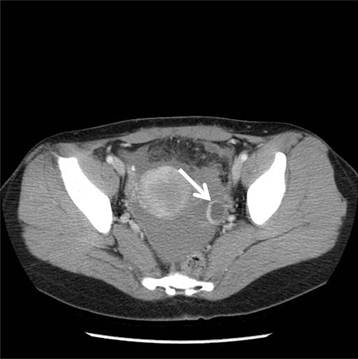

She was hemodynamically stable. Her hemoglobin level was 13.1 g/dL, and the white blood cell count was 5.9 × 109/L. A coagulation test conducted showed normal results. Urinary pregnancy test was negative, and computer tomography scan showed fluid collection and cyst formation in the left ovary (Fig. 1). Culdocentesis confirmed hemoperitoneum. On the basis of her clinical manifestations, hemoperitoneum secondary to the ovarian cyst rupture was suspected, and laparoscopic surgery was planned. During laparoscopy, more than 500 ml of blood and blood clots were evacuated. A 2-cm large left ovary cyst was noted, but there was no bleeding in both the ovaries and fallopian tubes. Hematoma in the omentum was noted, but there was no omental bleeding. On examining the sigmoid colon, a diverticulum, 10 × 2 × 1 mm in size was found, and the bleeding focus was identified in the proximal part of the sigmoid colon (Fig. 2). No evidence of intraluminal bleeding was noted; however, the diverticulum site could not be clearly examined during intraoperative colonoscopy owing to incomplete bowel preparation. The bleeding was controlled by #3-0 Vycryl intracorporeal suture, and the invagination of the diverticulum was performed laparoscopically. The recovery was uneventful, and the patient was discharged on postoperative day 4.

Fig 1

Fluid collection and left ovary cyst was noted on computed tomography. The size of ovary cyst was 2.0 × 1.8 cm (arrow).